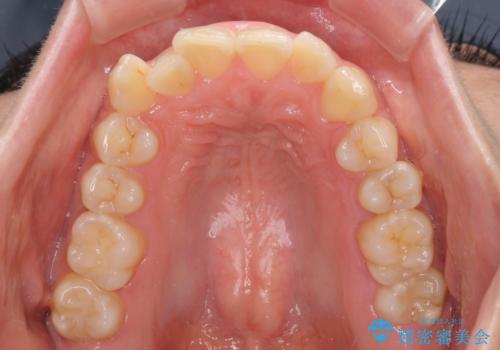

- 上下前歯のデコボコを気にして来院された患者様です。

デコボコが強いため、非抜歯で矯正をすると出っ歯仕上がりとなるため、上下左右の第一小臼歯4本を抜歯することとしました。